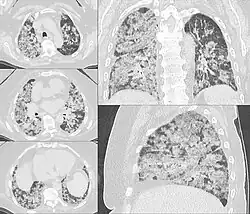

Diffuse hemorrhage from the alveoli in the lungs

Pulmonary